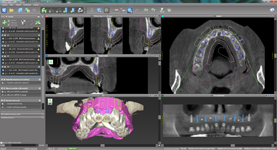

coDiagnostiX

Jedná se o externí plánovací program, spojený se zubní laboratoří a frézovacím centrem, který využívá dat získaných z 3D rentgenu čelisti, otisku zubů a dásně (scanu zubů a dásně) a finálního návrhu protetické náhrady. Tento program umožňuje tříprostorovou počítačovou simulaci při plánování pozic implantátů. Součástí programu je i databáze, ve které mohou být uloženy všechny typy implantátů od všech výrobců, včetně jejich délek, průměrů i tvarů.

Lékař si vytvoří všechny typy zobrazení potřebných pro naplánování – tedy 2D snímky (panoramatický), příčné řezy i 3D model.

Vidí zde i důležité anatomické útvary – čelistní dutinu, průběh nervu atd. Po proměření množství kosti – šířky i výšky vybere z databáze vhodný typ implantátu a umístí ho do požadované lokality. Ihned vidí jeho pozici ve všech 3 rovinách a na všech snímcích i 3D modelu. Může upravovat podle potřeby jeho pozici, sklon atd.

Všechny vybrané a správně umístěné simulované implantáty se ukládají do „počítačové karty“ pacienta s jejich pozicí, délkou, průměrem, typem i sklonem. V programu také lékař navrhuje chirurgické šablony pro řízenou nebo navigovanou implantaci. Lékař i pacient tedy ještě před vlastní operací vidí, jak by mělo ošetření probíhat a vypadat.